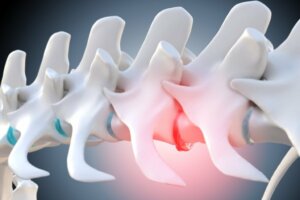

Koirien tapauksessa kipu sijaitsee kolmessa viimeisessä lannenikamassa (L5-L6-L7) ja ristiluussa, joka yhdistää lantion selkärankaan. Sen lisäksi, että alaselkäkipu vaikuttaa luustoon, se lisää myös alueen lihastyötä, mikä aiheuttaa kipua ja jäykkyyttä liikuntaelimistössä.

Tämä johtuu itse kipumekanismista, joka aktivoi elimistön tulehdusprosessit puolustuskeinona. Tämä lihasten tulehdus puolestaan painaa hermoratoja aiheuttaen puristusta tai jopa välilevyn pullistumia ja välilevytyriä.